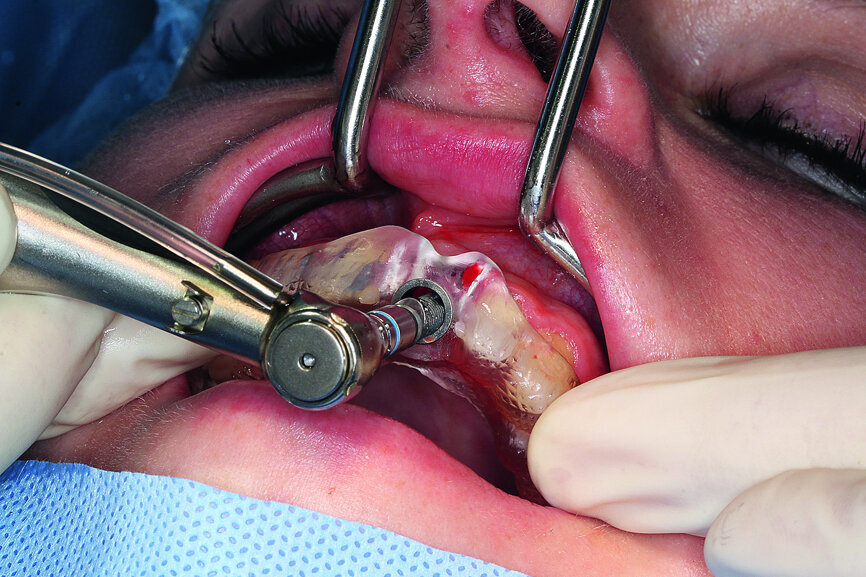

Fig. 9: Preparing the implant bed according to the recommended drill sequence, insertion of the implant using the SICAT surgical guide.

When extracting tooth #21, it was important to preserve the vestibular lamina to allow immediate implantation. For this reason, the Sharpey’s fibres were carefully severed with a periotome, and the tooth was gently removed (Fig. 7). The tooth had pronounced dentinal resorption, confirming the previously made diagnosis (Fig. 8). The SiroLaser Blue (Dentsply Sirona) with a wavelength of 970 nm was used to disinfect the alveolus. An OsseoSpeed EV 4.8–15 mm implant (Astra Tech Implant System, Dentsply Sirona) was inserted immediately using a surgical guide (SICAT OPTIGUIDE, SICAT; Fig. 9). At > 35 Ncm, sufficient primary stability was achieved.